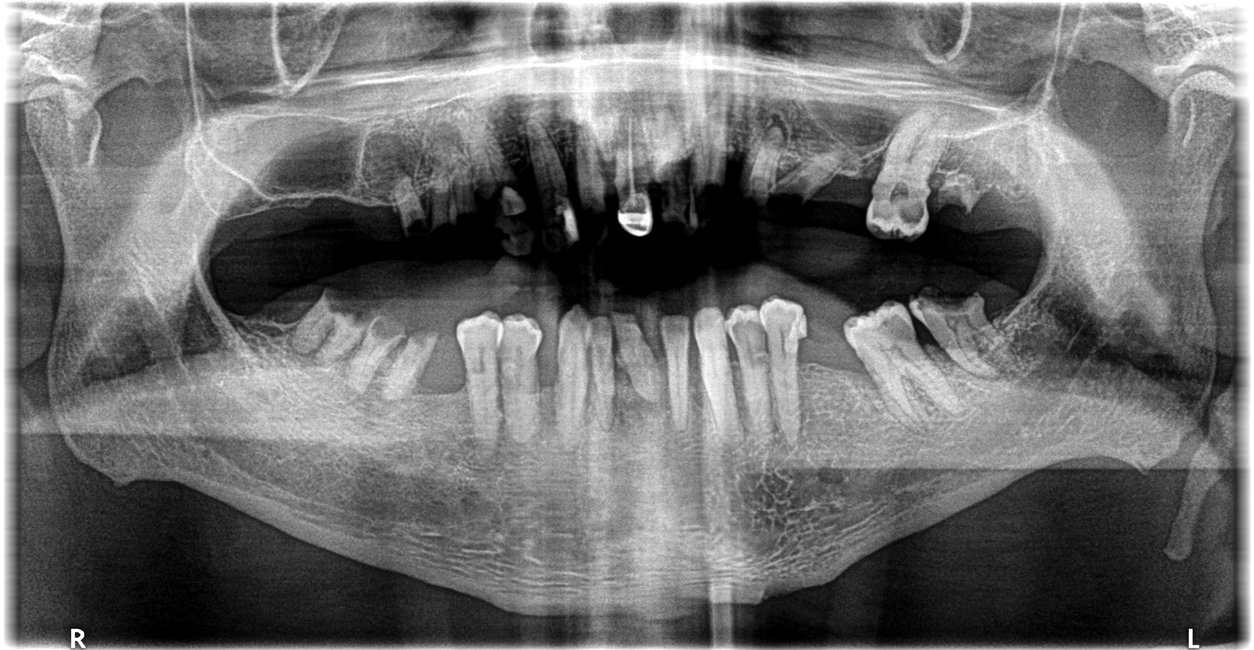

Figure 2: These re-operative panoramic radiograph.

Figure 2

Figure 15: A pre-operative panoramic radiograph reveals several issues.

Figure 15